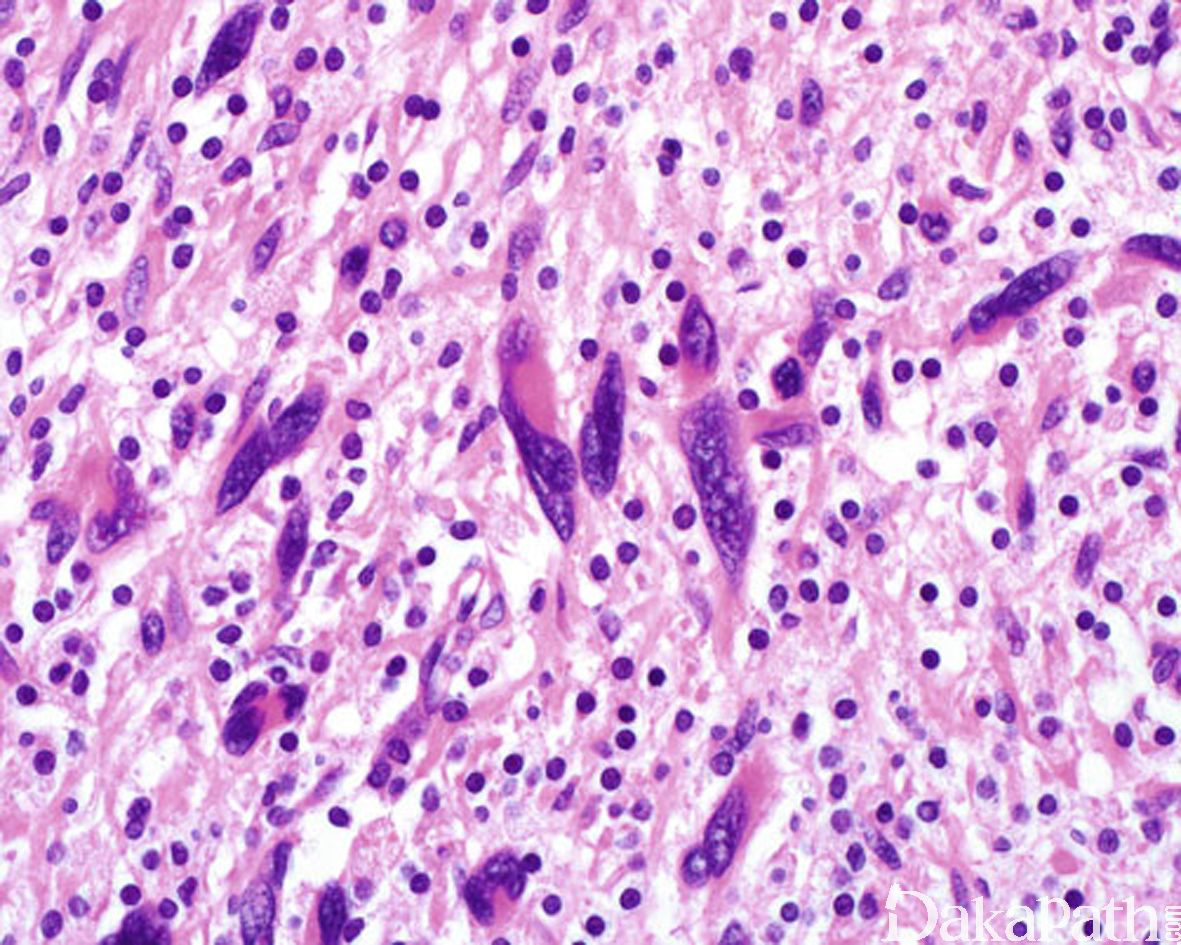

在神经纤维瘤形态学结构基础上,出现散在、核大、染色质呈污浊状,核仁不明显,核内可见胞质性的包涵体的核异型细胞,无核分裂像。